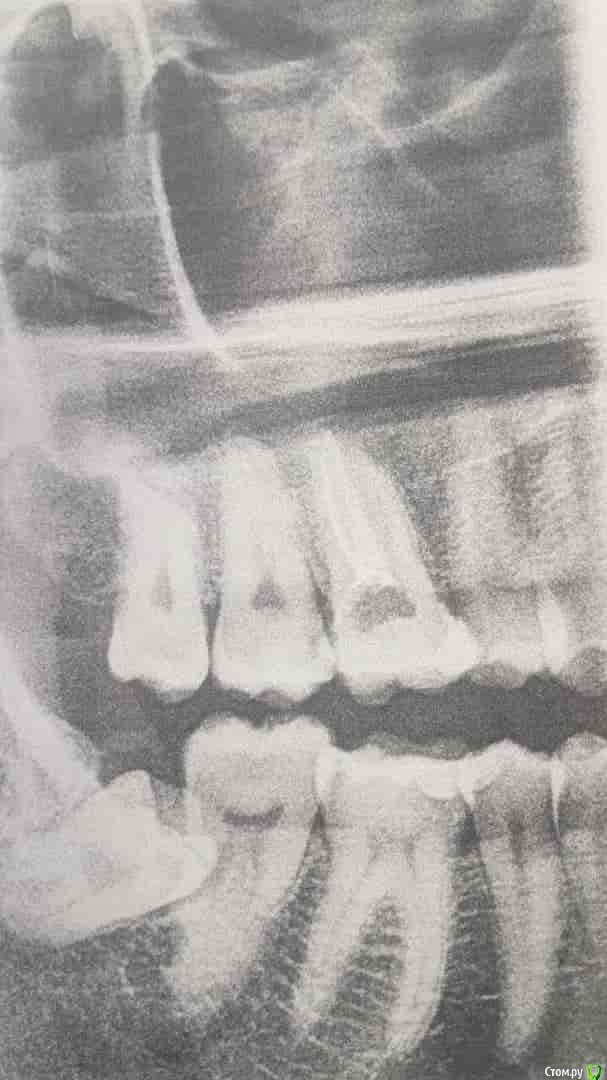

aleksei_sataev Опубликовано 21 апреля, 2019 Поделиться Опубликовано 21 апреля, 2019 (изменено) Добрый вечер уважаемые стоматологи. Примерно месяц назад на верхней 6-ке произошел скол небольшой. Обратился не сразу, спустя 2-3 недели, когда 2 раза ночью тревожили ноющие боли. У стоматолога выяснилось, что за это время нерв погиб, его убрали, оставили лекарство на 2 недели с временной пломбой. Сегодня прочистили 2 канала из 3, в 2 поставили пломбы-штифт, в 3-ю не стали, т.к. там были следы воспаления, секрет. Поставили временную пломбу на зуб и сказали 3 канал завершим через 2 недели, мол пока нельзя пломбировать, т.к. может воспалиться челюстьПри этом до скола зуба с этой стороны иногда был пузырь под десной, откуда переодически выходила жидкость с запахомВопрос в следующем, нормально ли что месяц лечим зуб? Снимок сделал сам, в другой клинике.Всё ли в порядке сейчас?https://cloud.mail.ru/public/48ND/2Rn6BcMY1 Изменено 21 апреля, 2019 пользователем aleksei_sataev Ссылка на комментарий

aleksei_sataev Опубликовано 24 апреля, 2019 Автор Поделиться Опубликовано 24 апреля, 2019 Который лечется зуб фиг с ним))) А вот который лежит зуб мудрости его под удаление или можно походить с ним? Ссылка на комментарий

red_butler Опубликовано 30 апреля, 2019 Поделиться Опубликовано 30 апреля, 2019 А вот который лежит зуб мудрости его под удаление или можно походить с ним? удалять Ссылка на комментарий